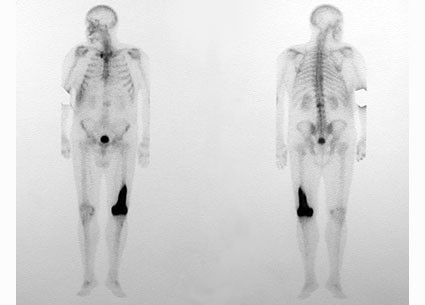

El hallazgo de esta enfermedad debe ser seguido por una completa evaluación clínica del paciente. La centellografía ósea con Tc99m permite establecer la extensión del compromiso óseo (enfermedad monostótica, oligostótica o poliostótica) para luego radiografiar en detalle los huesos afectados (ver la Fig. 80-1).

Fig. 80-1. Centellograma óseo de cuerpo entero (la porción izquierda de la figura es la vista anterior del esqueleto, y la porción derecha la vista posterior). Se observa la acumulación del trazador en el extremo distal del fémur izquierdo.